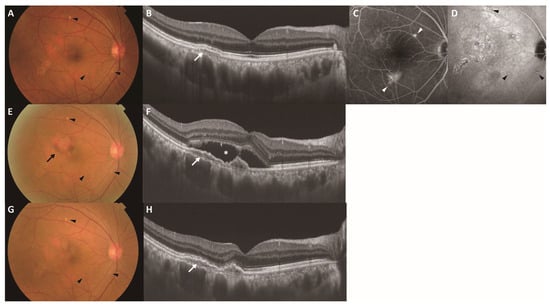

Five-Year Changes in Pachydrusen with Late-Phase Hyperfluorescence on Indocyanine Green Angiography

by Hiroyuki Kamao, Katsutoshi Goto, Kenichi Mizukawa, Ryutaro Hiraki, Atsushi Miki and Shuhei Kimura

J. Clin. Med. 2026, 15(8), 2836; https://doi.org/10.3390/jcm15082836 (registering DOI) - 9 Apr 2026

Background/Objectives: Pachydrusen are a drusen subtype associated with the pachychoroid disease spectrum; however, their long-term natural history and pathophysiological significance remain unclear. We investigated 5-year morphological and topographic changes in pachydrusen using diagnostic criteria incorporating late-phase indocyanine green angiography (ICGA) hyperfluorescence. Methods: This retrospective observational study included fellow eyes with pachydrusen from patients with unilateral neovascular age-related macular degeneration. Pachydrusen were defined as sub-retinal pigment epithelium (RPE) deposits ≥ 125 µm in size with corresponding hyperfluorescence on late-phase ICGA. Lesion number, size, and spatial distribution (ETDRS grid and quadrant-based classification) were evaluated at baseline and 5 years. The incidence of macular neovascularization (MNV) and its colocalization with pachydrusen were assessed. Results: Among 57 fellow eyes with pachydrusen, incident MNV developed in 8 eyes (14.0%) during follow-up; the mean time to onset was 25.6 ± 16.3 months. No clear colocalization between pachydrusen and incident MNV was observed. Nineteen eyes completed the 5-year follow-up period. Pachydrusen were predominantly located outside the 6000 µm ETDRS grid at baseline (63.4%) and 5 years (66.3%), significantly exceeding the expected proportion based on the area ratio (p < 0.001). The lesions were most frequently observed in the superotemporal quadrant (52.6%). Over 5 years, 19.8% of the lesions increased in size, 67.2% remained stable, and 12.9% regressed; none of the regressed lesions were accompanied by RPE atrophy. Conclusions: Pachydrusen, defined as late-phase ICGA hyperfluorescence, was predominantly distributed outside the ETDRS grid with a superotemporal predilection and could increase or decrease over a 5-year follow-up period. No colocalization with MNV was observed, and no accompanying RPE atrophy after pachydrusen regression was identified, suggesting that late-phase ICGA–hyperfluorescent pachydrusen may represent a pathophysiology distinct from that of soft drusen. Full article

Show Figures

Figure 1